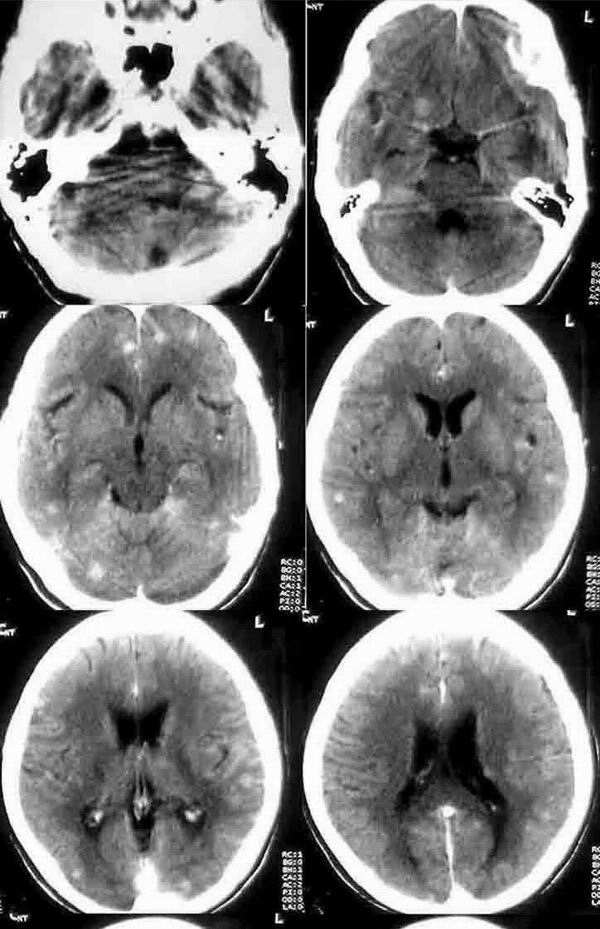

增强:脑内广泛多发结节影.多位于皮质和皮髓质交界区,强化明显.ct值达86.5hu.

57岁,女性,双侧大脑半球皮髓质交界处多发大小不等的结节影,高密度,未见明显水肿,首先考虑转移瘤,建议行胸部检查,有些肺癌脑转移可有类似表现。

平扫仅见二个结节,但增强见有多发结节,且大多位于皮髓交界,未见明显钙化,年龄57岁,我认为首先考虑转移性肿瘤,不完全除外结核结节。

幕上幕下皮质及皮质下区多发散在等密度结节病灶,无水肿及占位,明显强化。

本例皮层及皮髓交界处的多发等高密度无水肿结节,考虑脑转移瘤可能性更大一些。

因为无水肿,而区别于结核肉芽肿,部分肺及骨的恶性肿瘤脑转移灶可无水肿,而无水肿的结核肉芽肿更少;结核肉芽肿多位于脑浅表部位,皮髓交界处很少见,而脑转移瘤更多位于此处(分水岭);结核肉芽肿平扫密度应更一致而非此例为等密度及稍高密度,增强扫描多为环形、结节形或不均匀强化,而非此例均匀性强化;结核性肉芽肿多伴有脑积水、脑梗塞,脑底池往往有较特征性的强化。